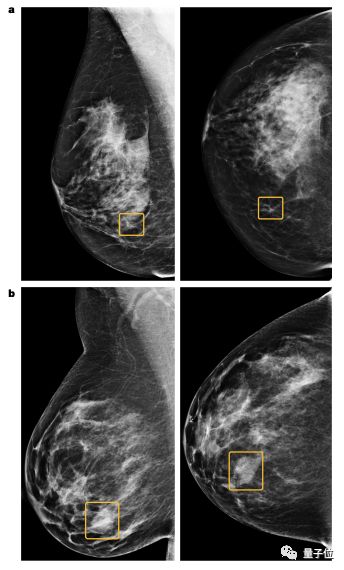

a图中的小型的不规则钙化结构被AI识别出来,但是6位放射科医生都没有识别出来

b图中的大密度块状恶性肿瘤被6位放射科医生识别出来,但是AI却没有识别出来

总体而言,AI捕捉的癌症比医生捕捉的更有侵入性。研究者尚未对此作出解释。